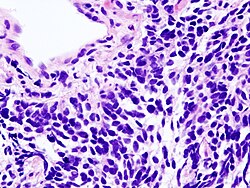

Karcinomi pluća se klasificiraju prema histološkom tipu.[8] Ova klasifikacija je važna za određivanje liječenja i prognozu ishoda bolesti. Većina zloćudnih tumora pluća su karcinomi, zloćudni tumori koji potječu od epitelnih stanica. Karcinomi pluća se svrstavaju na osnovi izgleda zloćudnih stanica koje određuje patolog, pomoću mikroskopa. Dvije najšire skupine su ne-sitnostanični i sitnostanični karcinomi pluća.[44]

Sitnostanični karcinom pluća

Stanice sitnostaničnog karcinoma pluća (SCLC) sadrže gusta neurosekretorna zrnca (vezikule koje sadrže neuroendokrine hormone), zbog čega su s ovim tumorom povezani endokrini/paraneoplastični sindromi.[47] Većina ih nastaje u velikim i srednje velikim bronhima (prvog i drugog reda).[10]Ovi karcinomi rastu brzo i metastaziraju rano tijekom bolesti. U doba postavljanja dijagnoze metastaze postoje u šezdeset do sedamdeset posto bolesnika. Ovaj tip karcinoma pokazuje jaku povezanost s pušenjem.[1]